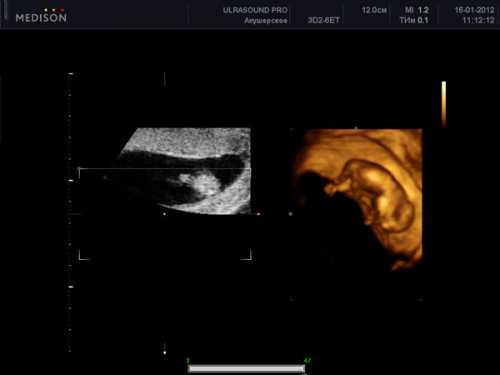

Если беременность вторая и последующая, то живот может уже существенно округлиться. Это обусловлено тем, что мышцы и связки за предыдущую беременность уже хорошо растянулись, поэтому они эластичны и подвижны. После недель беременности размер живота может зависеть и от других факторов, таких как телосложение, место прикрепления плаценты и количество плодов. Нормальными выделениями во время беременности считаются прозрачные, белые и желтоватые без примеси гноя и крови, а также резкого запаха. Если наблюдается существенное увеличение их объема, изменение цвета и консистенции, а также появление жжения и зуда, следует обратиться к гинекологу для постановки правильного диагноза. Опасным симптомом является появление значительных по объему кровянистых выделений, сопровождающихся резкой схватко образной болью в нижней части живота и в области поясницы. Такая симптоматика в срок беременности недель может свидетельствовать об отслойке плаценты и начавшемся выкидыше. ая неделя беременности это период обязательного первого скрининго вого обследования, которое позволяет оценить жизнеспособность плода, его состояние и развитие, место прикрепления к плаценте, а также наличие или отсутствие генетических нарушений или отклонений. вес и размеры плода структуру головного мозга правильное расположение внутренних органов малыша окружность головы и живота. Если во время двенадцатой недели беременности ощущения в животе отклоняются от нормы, а также выявляются какиелибо проблемы, будущая мама должна пройти дополнительные обследования. Для подтверждения диагноза синдром. Дауна в период недели проводится специальный анализ, способный провести точное определение вероятности рождения ребенка с таким отклонением. В зависимости от размера и веса плода врач также устанавливает предполагаемую дату родов. Живот на двенадцатой неделе беременности увеличивается, плод подрастает еще больше. Рост малыша составляет около мм, а вес варьируется в пределах г. Будущий ребенок по размерам как лимон.

Его сердце бьется с частотой около ударов в минуту, что можно услышать при проведении ультразвукового обследования. Плод уже умеет поднимать и опускать грудь, словно дышит, а также способен зажмуривать глаза, открывать ротик, шевелить пальцами на ногах и руках. Ребенок может сосать свой пальчик, глотать жидкость, мочиться, а также икать. К тому же он активно шевелится, но женщина еще не может почувствовать его движения, поскольку их смягчает плацента и амниотическая жидкость внутри. От срока беременности двенадцать недель у плода развивается вилочковая железа, отвечающая за выработку лимфоцитов.